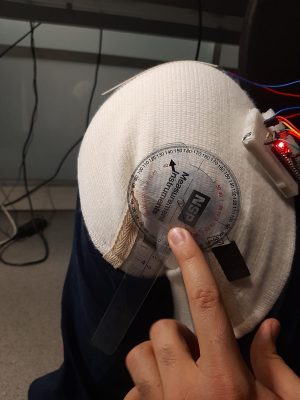

_ PROJECTS

Water Ejection System (iOS)